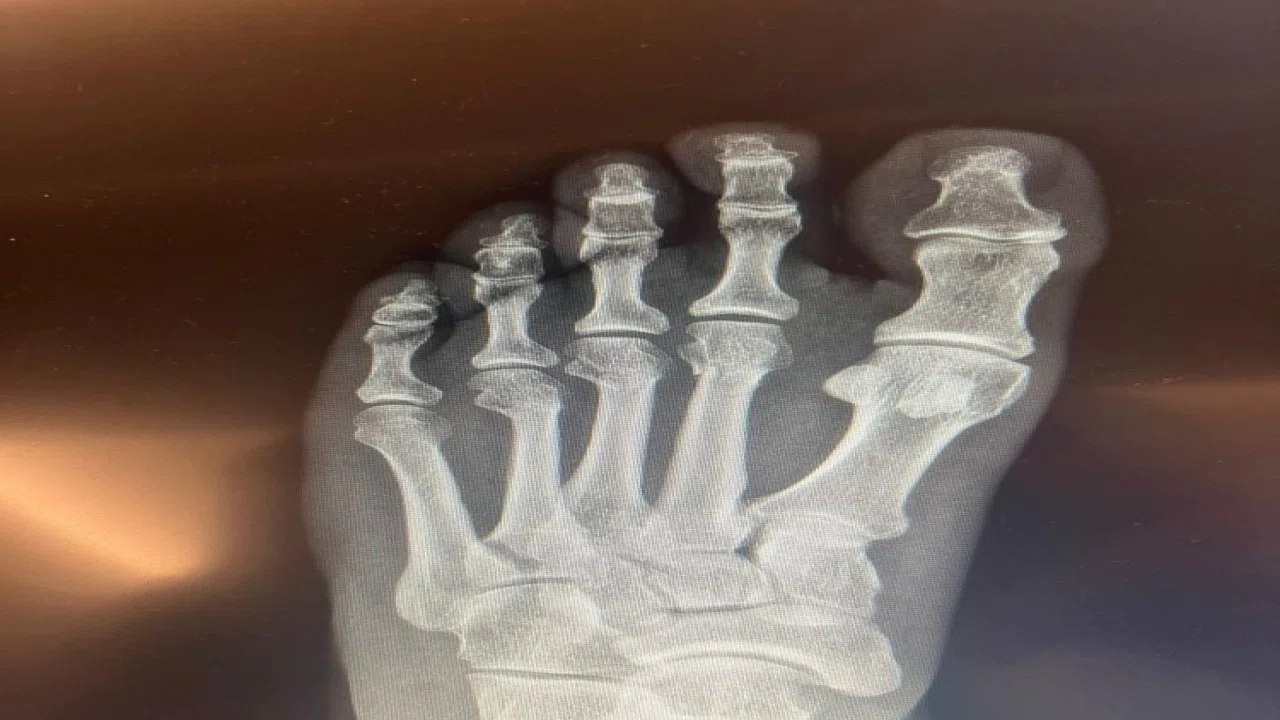

Anadolu'da Bugün Gündem Özel' den iddialara karşılık ayak röntgeni geldi!

Özel' den iddialara karşılık ayak röntgeni geldi!

Cumhuriyet Halk Partisi Genel Başkanı Özgür Özel, sosyal medyada yer alan ‘ayağından vuruldu’ iddialarına ilişkin, kırılan ayağının röntgen filmlerini paylaştı.

CHP Grup Başkanvekili Ali Mahir Başarır, geçen hafta TBMM'deki özel oturum öncesi gazetecilere yaptığı açıklamada, CHP Genel Başkanı Özgür Özel'in evde geçirdiği kaza sonucu ayağında ufak çaplı kırılma olduğunu duyurmuştu.

Özel’in ayağında oluşan kırık hakkında sosyal medyada, Özel'in ‘ayağından vurulduğu’ iddiaları yer almıştı. Özel, tartışmalara ilişkin ayağının röntgen filmlerini paylaştı.